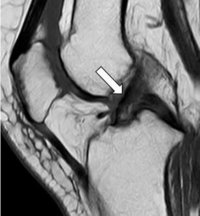

問診、診察に続き画像検査を行います。ACLは単純エックス線写真に写らないため、MRI(磁気共鳴画像装置)検査を行います。MRIでACLの描出が不明瞭ないしは描出されないときは損傷を疑います。またMRIでは、他の靭帯損傷の有無や半月板損傷の有無の確認を行います。